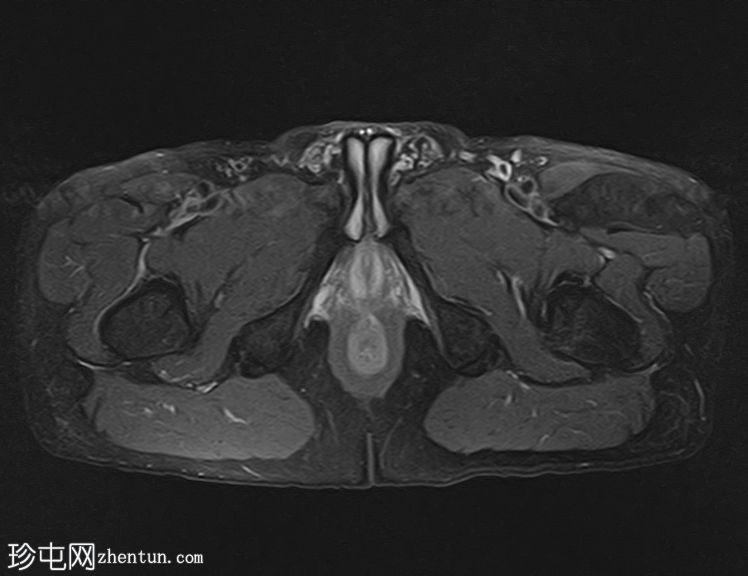

轴位

PDFS序列

左侧股直肌近端至中段肌纤维内可见一长条状、边界清晰的肌内肿块,其大小约为:头尾径14.4 cm,横径6.6 cm,前后径2.7 cm。

该病灶在所有序列上均呈脂肪信号,T1加权像上呈高信号,脂肪抑制像上信号完全抑制(假性高信号)。

未见厚间隔、结节状结构或非脂肪成分。